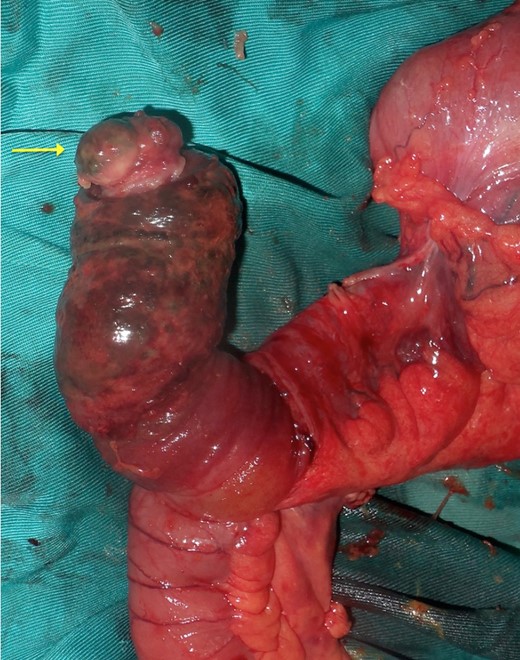

Upon laparotomy, we found an ileocecal intussusception, with mesenteric lymphadenopathies and a dilation of the whole small bowel (Fig. 3). We performed a right hemicolectomy, without attempting to reduce the intussusception, and an end-to-end ileotransverse anastomosis.